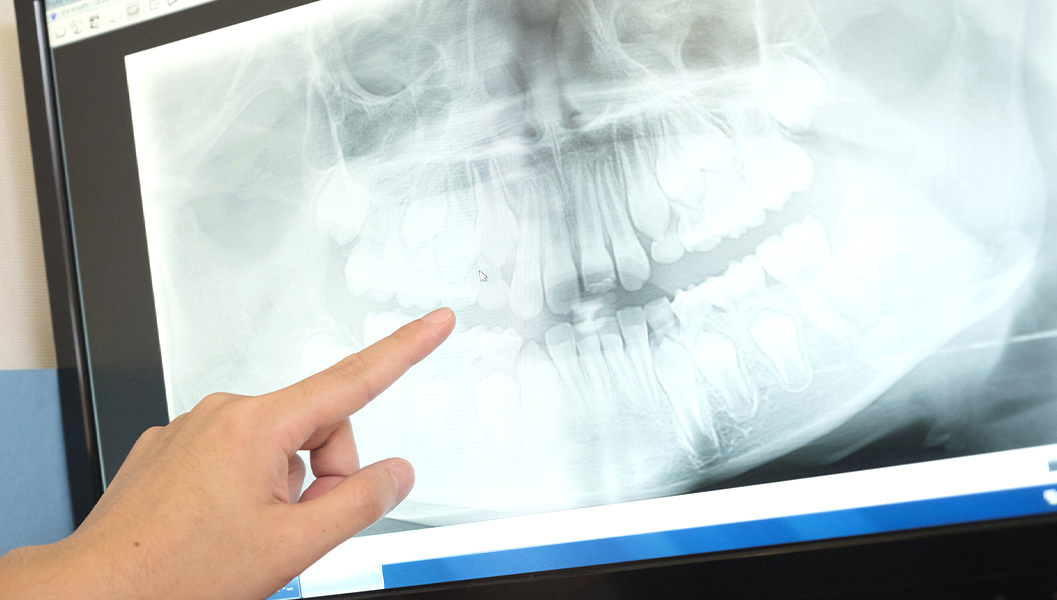

虫歯の検査

検査器具やレントゲンで、虫歯の進行度合いを調べます。